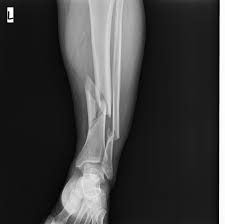

Sınırlı girişimsel plak tespiti sıklıkla metafizyel yerleşimli (üst ve alt uç bölgeler) parçalı kırıklara uygulanmaktadır. Parçalı ve basit metafizyel kırıkların düşük profilli plaklar ile medial krural bölgeye, subkutan tünelleme ile tespiti esastır. Düzeltme, koronal-sagittal ve rotasyonel dizilimin sağlanması koşulu ile kabul edilir, anatomik dizilim zorunlu değildir. Tespit sertliği göreceli denge olarak bilinen, mikro harekete izin veren düzeydedir. Mikrokareket özellikle parçalı kırıklarda uygun miktarda kullanılabilirse kırık kaynamasına olumlu etkide bulunmaktadır.